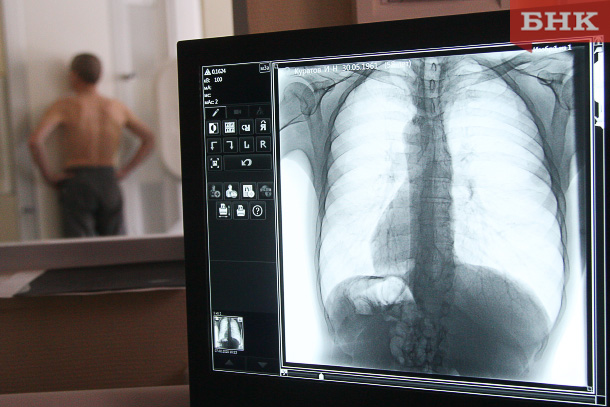

Врач рассказал о способах выявления рака легкого на ранней стадии

Врач-онколог высшей квалификационной категории, торакальный хирург Андрей Нефедов рассказал, как обнаружить рак легкого на ранней стадии.